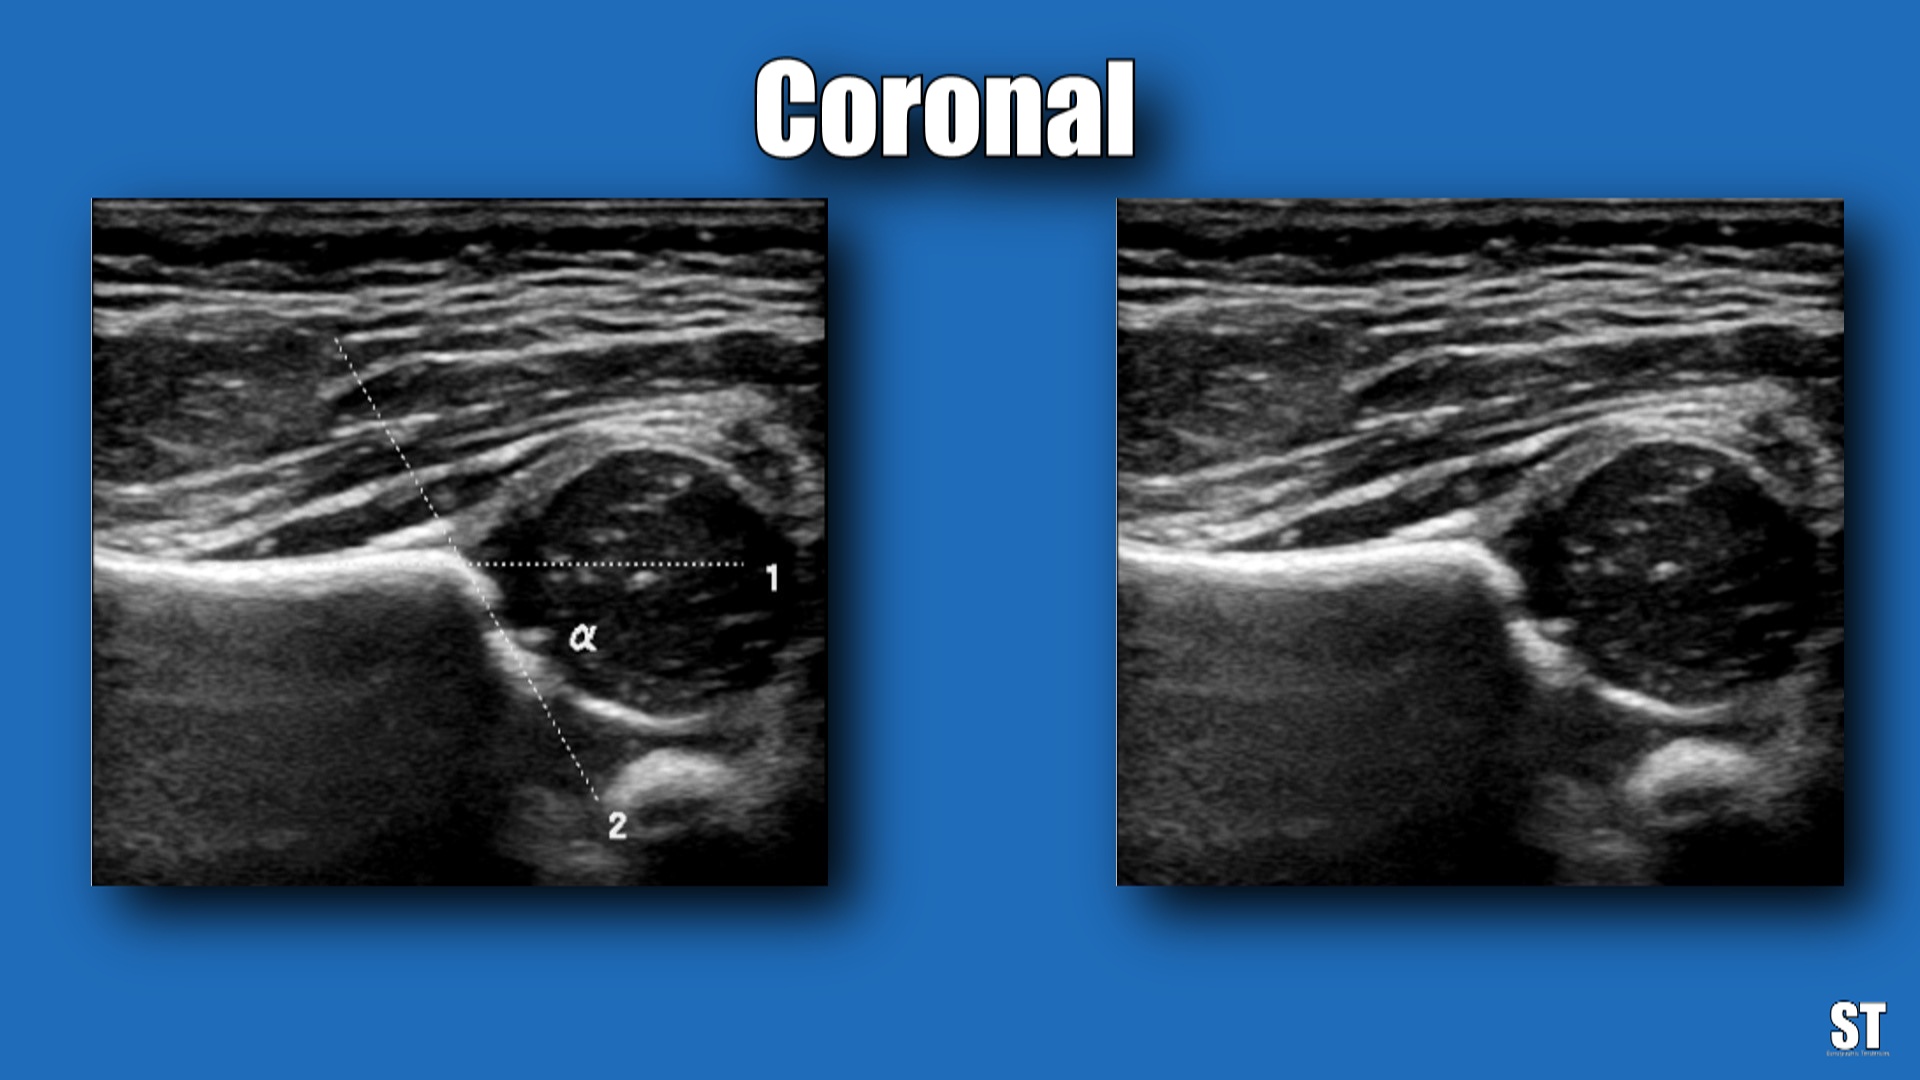

From sonographictendencies.com

Neonatal Hip Ultrasound Sonographic Tendencies Baby Hip Ultrasound Protocol A stepwise approach will be shown in this article. The graf method is the most widely used ultrasound technique for infant hips; This document provides guidelines for the performance and recording of ultrasound examinations for detection and assessment of. It affords direct visualization of the cartilaginous and other. Learn how to perform and interpret paediatric hip ultrasound images for neonates.. Baby Hip Ultrasound Protocol.

Neonatal Hip Ultrasound Sonographic Tendencies Baby Hip Ultrasound Protocol This document provides guidelines for the performance and recording of ultrasound examinations for detection and assessment of. Ultrasound is the preferred method for diagnostic imaging of the infant hip [5,6]. The graf method is the most widely used ultrasound technique for infant hips; See the normal anatomy, angles, criteria and limitations of the. It affords direct visualization of the cartilaginous. Baby Hip Ultrasound Protocol.

Neonatal Hip Ultrasound Sonographic Tendencies Baby Hip Ultrasound Protocol Learn how to perform and interpret paediatric hip ultrasound images for neonates. It affords direct visualization of the cartilaginous and other. See the normal anatomy, angles, criteria and limitations of the. A comprehensive guide for clinicians, radiographers and radiologists who perform and report on paediatric hip scans using ultrasound imaging. Ultrasonography (us) is a useful screening method for the diagnosis. Baby Hip Ultrasound Protocol.

Neonatal Hip Ultrasound Sonographic Tendencies Baby Hip Ultrasound Protocol Developmental dysplasia of the hip is a congenital disorder in which the acetabulum is underdeveloped or there is. This document provides guidelines for the performance and recording of ultrasound examinations for detection and assessment of. Ultrasound is the preferred method for diagnostic imaging of the infant hip [5,6]. Ultrasonography (us) is a useful screening method for the diagnosis of developmental. Baby Hip Ultrasound Protocol.

From sonographictendencies.wordpress.com

Neonatal Hip Ultrasound Sonographic Tendencies Baby Hip Ultrasound Protocol A stepwise approach will be shown in this article. This document provides guidelines for the performance and recording of ultrasound examinations for detection and assessment of. It affords direct visualization of the cartilaginous and other. Learn how to perform and interpret paediatric hip ultrasound images for neonates. Developmental dysplasia of the hip is a congenital disorder in which the acetabulum. Baby Hip Ultrasound Protocol.